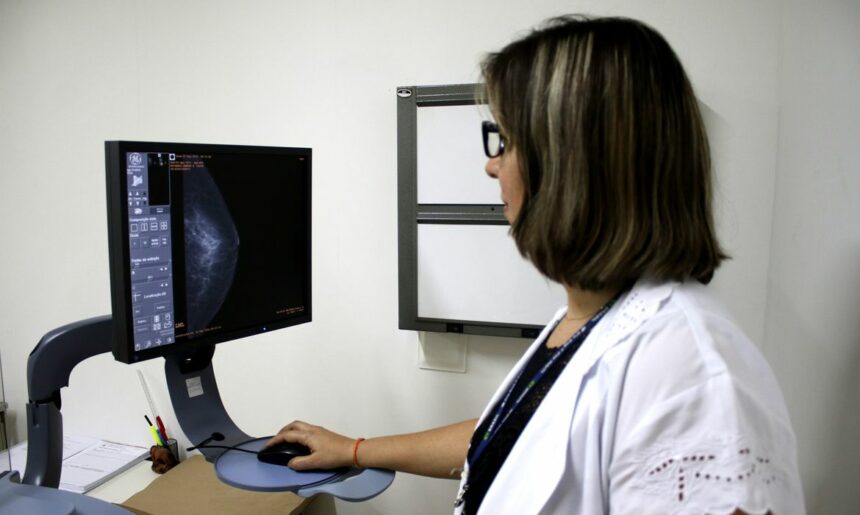

Um dos principais critérios é a realização de rastreamento organizado, ou seja, a convocação das usuárias para realizarem exames regularmente, mesmo sem sintomas. No caso do câncer de mama, a cartilha seguiu o protocolo do Ministério da Saúde e do Instituto Nacional do Câncer (Inca): mamografias a cada dois anos para as mulheres com idades entre 50 e 69 anos.

Para as entidades médicas, a mamografia deve incluir essas pessoas, porque o diagnóstico de câncer em pessoas assintomáticas, a partir de exames de imagem, demanda tratamentos que impactam menos a qualidade de vida da paciente, e tem menos risco de recidivas, metástases e mortalidade.

O parecer ressalta que o cenário do rastreamento é melhor na rede privada, onde “53% dos tumores são detectados pela mamografia, em pacientes assintomáticas, e 40,6% são diagnosticados no estágio I (menos agressivo)”, logo não há risco de prejuízo para as usuárias que já têm indicação, caso mais mulheres sejam incluídas.